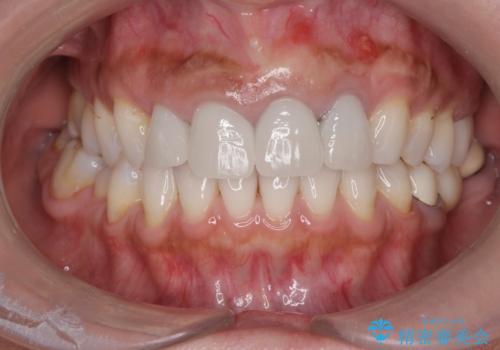

歯槽堤保存術を併用したブリッジ治療

- 前歯がグラグラし、においもする、とのことで改善を求めて来院されました。

一見して問題ないように見える左側の2前歯は、セラミックを除去してみると亀裂や虫歯の再発が見られました。

抜歯時に可及的に歯肉のボリュームを保つよう骨充填材とコラーゲン製剤による填塞を行い審美的かつ機能的なブリッジとなるよう治療を進めます。